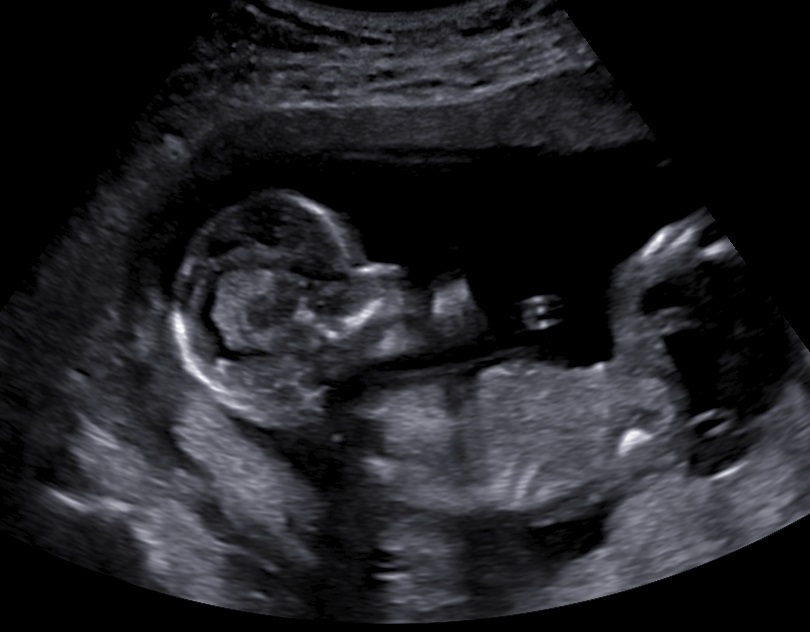

The fetus at 15+0 weeks of pregnancy was normal.